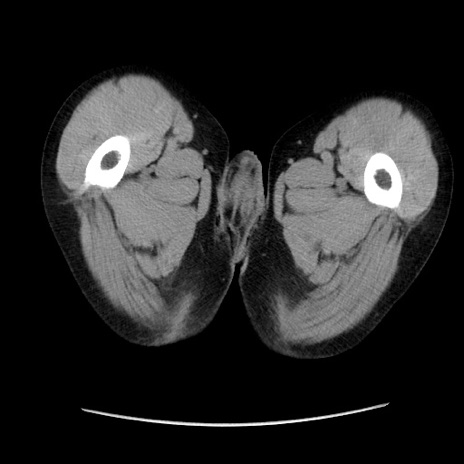

症例37(横断像)

【症例】40歳代 男性

【主訴】腹痛

【現病歴】4時間ほど前に電車に乗車中に臍部上より腹痛出現。徐々に増悪し起立困難となり、救急外来受診。生ものは数日食べていない。今朝お雑煮を食べた。

【身体所見】BT 36.8℃、BP 117/84mmHg、HR 91/min、SpO2 97%、苦悶様、腹部:臍上部広範囲圧痛あり、反跳痛±

【データ】WBC 8100、CRP 0.03